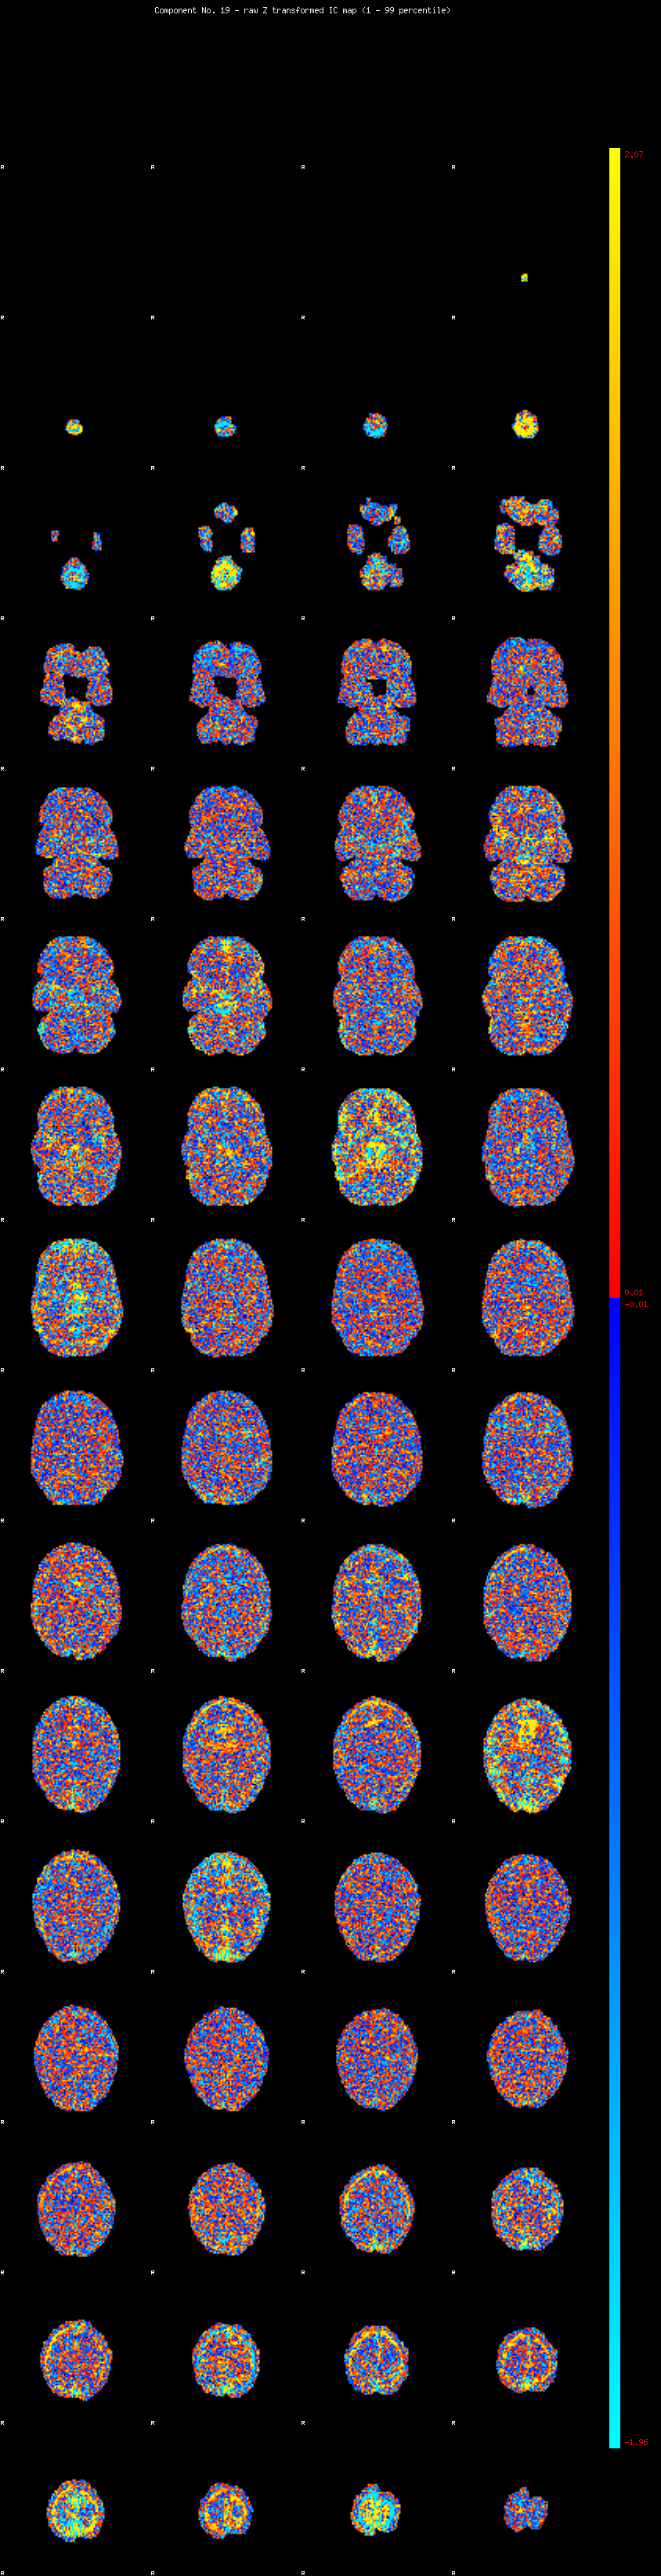

IC_19 Mixture Model fit

Means : -0.000000 3.194658 -2.728017

Vars : 1.000000 4.848854 2.941576

Prop. : 0.938754 0.033165 0.028080